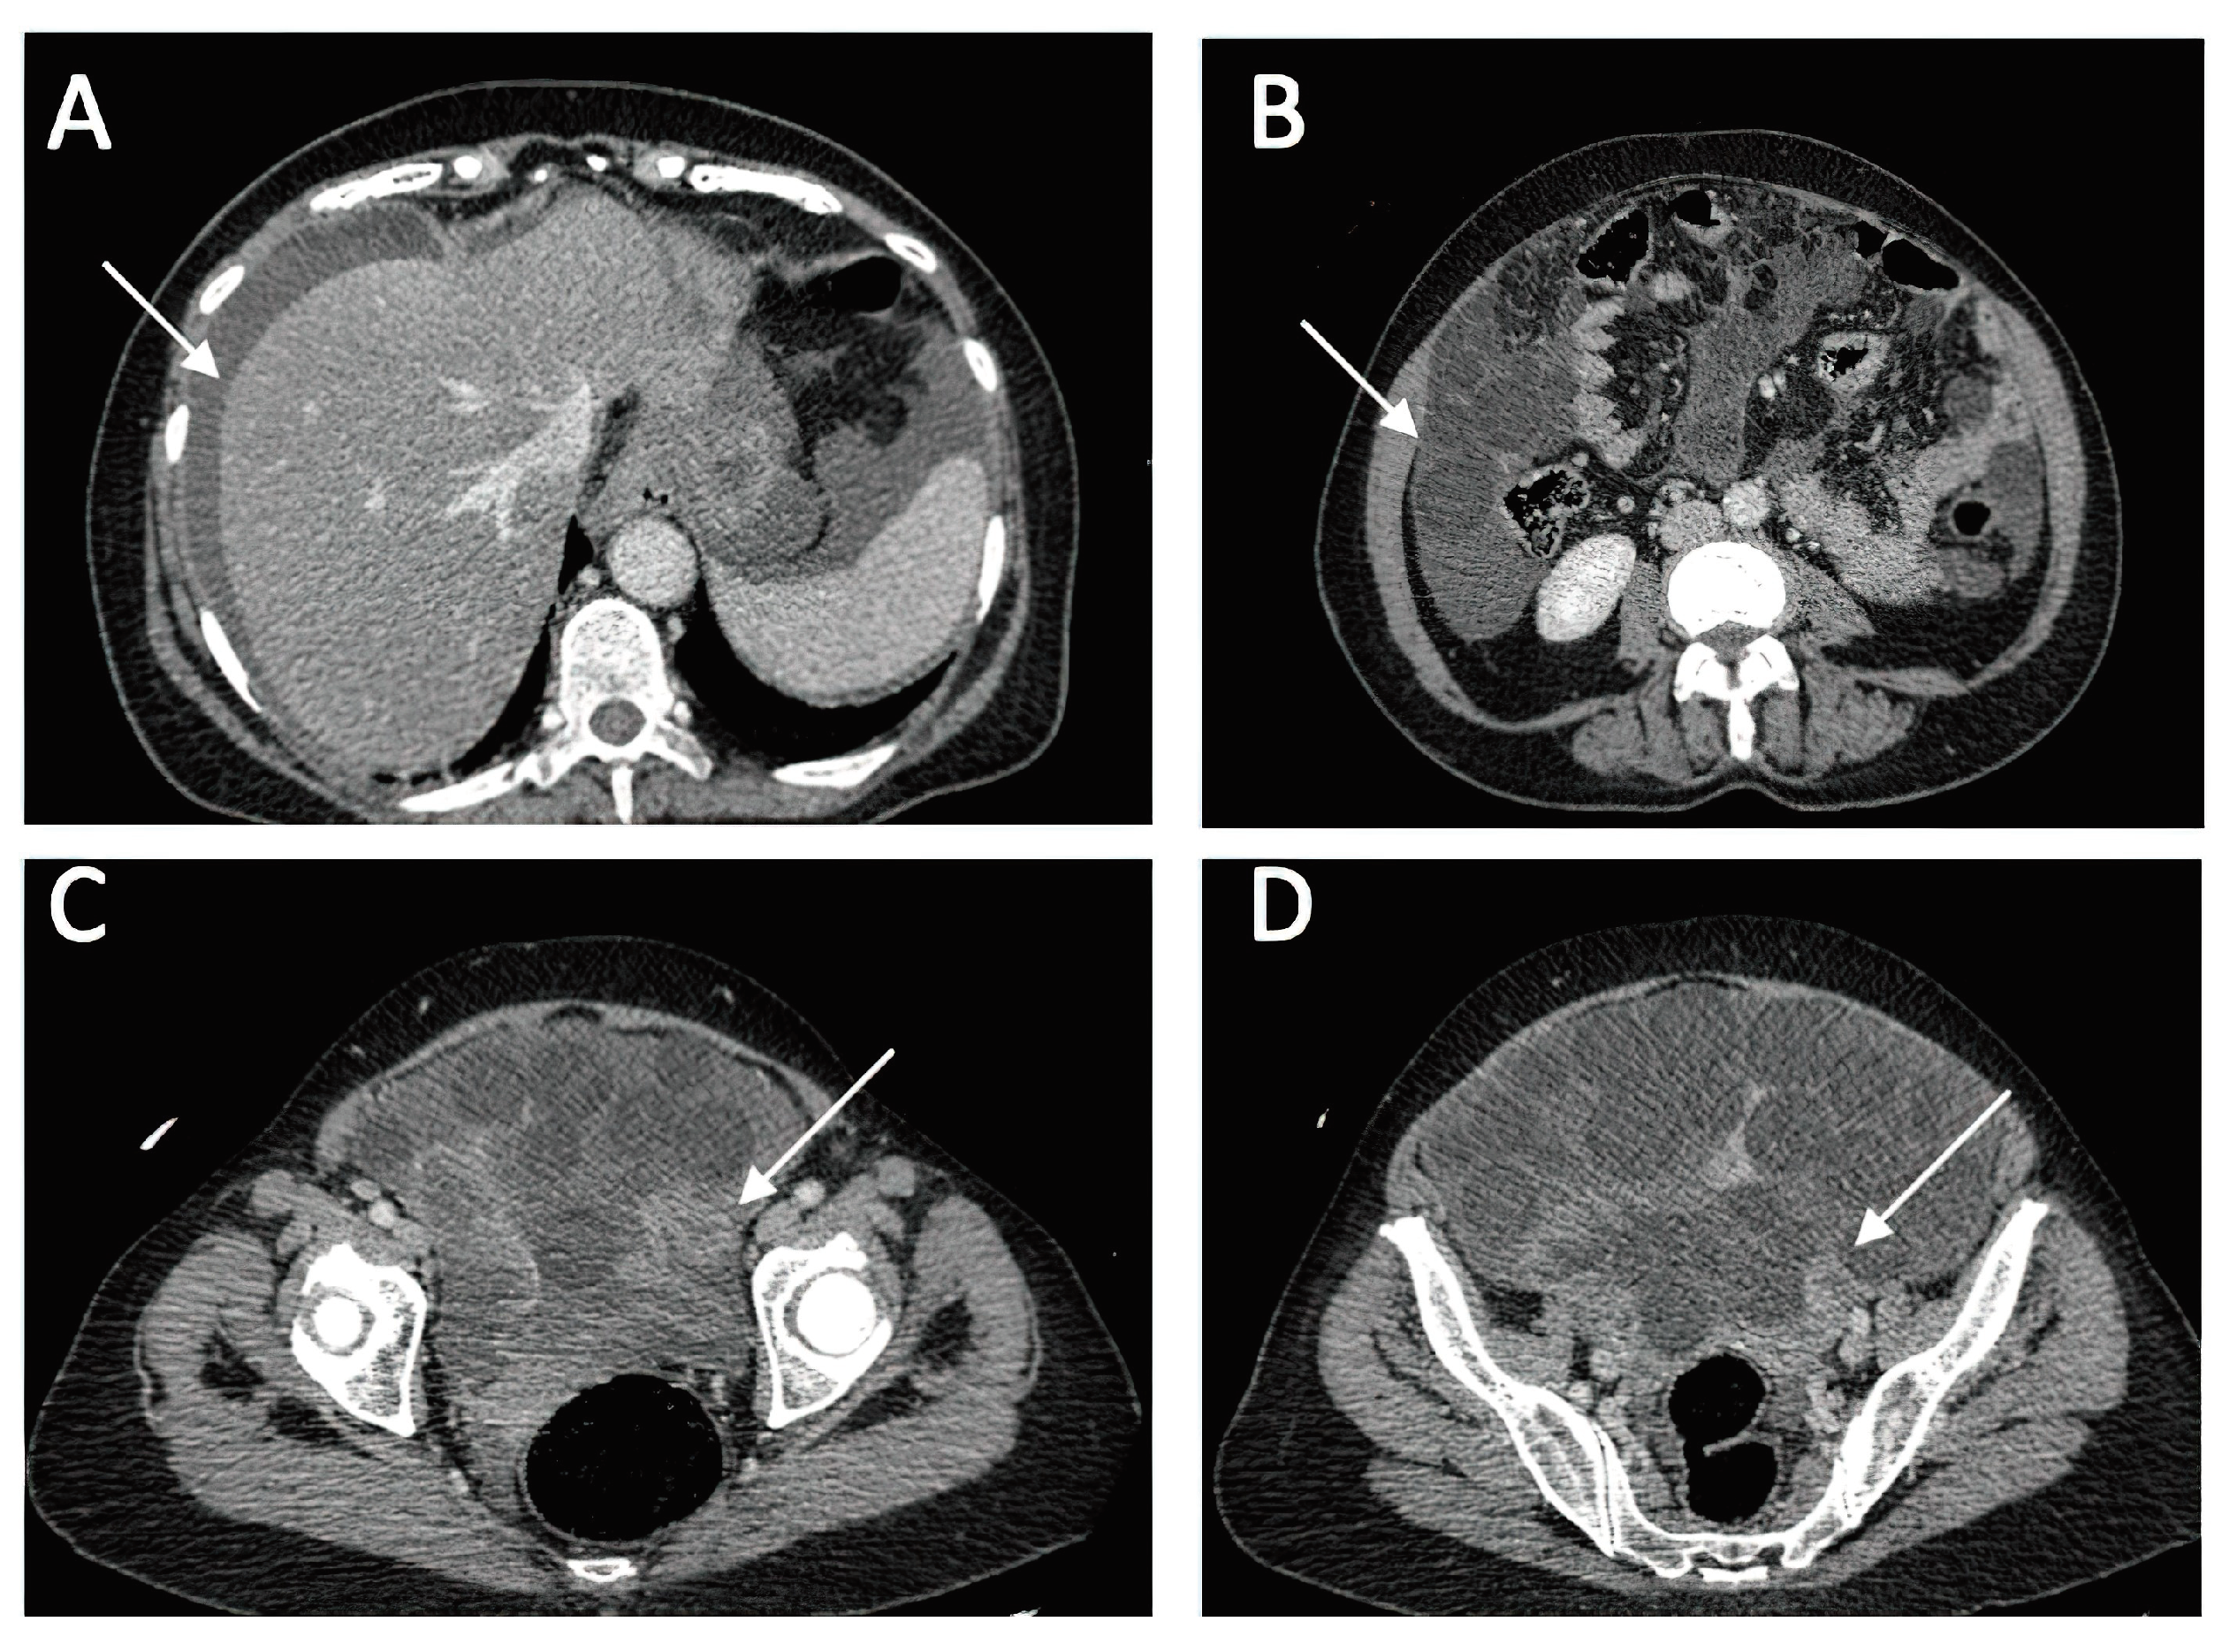

A CT investigation of the abdomen and pelvis was requested and performed. Radiology noted the presence of ascites in moderate amount, together with numerous round nodular lesions of varying sizes (between 1.5-4 cm), with no contrast uptake; the lesions were randomly distributed, with a slight prevalence for the pelvic region. However, a serpiginous lesion with intense contrast uptake was observed within the left ovary (Figure 1), leading the radiologist to falsely raise the suspicion of ovarian carcinoma with peritoneal carcinomatosis. The patient was hospitalized for additional investigations and medical treatment. After several days, an abdominal and pelvic MRI was also performed (Figure 2). Several ‘floating round bodies’ were observed throughout the whole peritoneum; the ‘floating bodies’ showed signal drop on the out-of-phase sequences suggesting fatty components. When analyzing the pelvic images, a ruptured cyst was observed across the right ovary. The diagnosis of ruptured ovarian teratoma was made and the patient underwent surgery. Left adnexectomy with peritoneal lavage and lysis of entero-enteric adhesions was performed. During the laparotomy, the peritoneal cavity was opened revealing a moderate amount of peritoneal fluid. A sample was then collected for cytologic examination. Macroscopically, the uterus had a normal appearance, with unremarkable right adnexa and left fallopian tube. As for the left ovary, a cystic mass with ruptured wall was observed. The cyst contained multiple well defined round lesions with fatty content, some of which were disseminated throughout the peritoneal cavity. The surgical findings are depicted in Figure 3.

Figure 1. Diagnostic CT Imaging of Abdominal and Pelvic Regions (a) ascites (b) multiple round intra-peritoneal fatty density lesions without contrast uptake; (c,d) serpiginous structure with intense contrast uptake at the level of the left ovary).